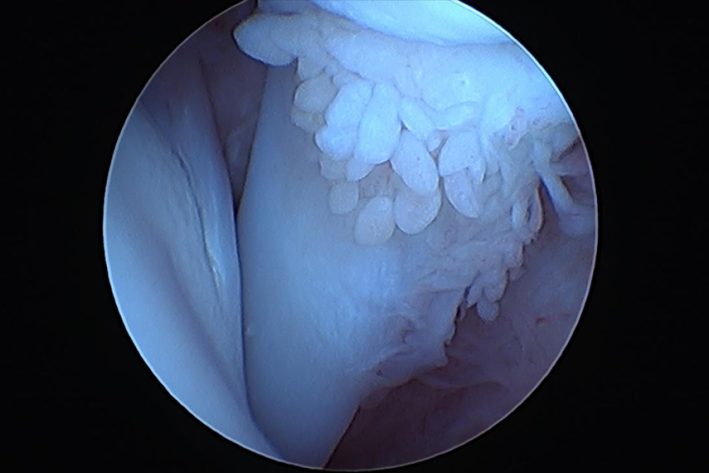

Arthoskopisches Bild einer gesunden Bizepssehne